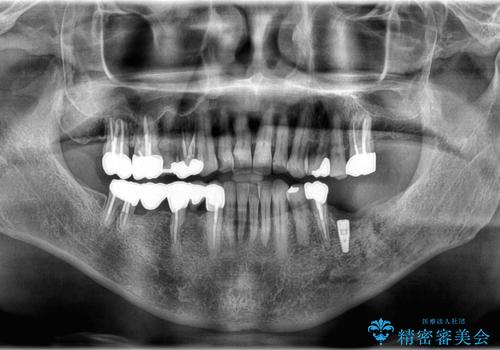

- 「奥歯の銀歯が取れた」を主訴に来院された患者さんです。

診査診断を行った結果、歯が折れた位置が深く、虫歯にもなっていたため抜歯後、インプラントで治療を行いました。

残根状態の歯を抜歯後、抜歯窩の治癒を待ちインプラントを埋入しています。

アバットメントの材質は咬合力を考慮しチタン合金にしました。

被せ物はオールセラミッククラウンを入れています。

患者さんから、インプラント埋入オペ後も痛みが殆どなく、咬めるようになったので治療をして良かったですと言って頂けました。